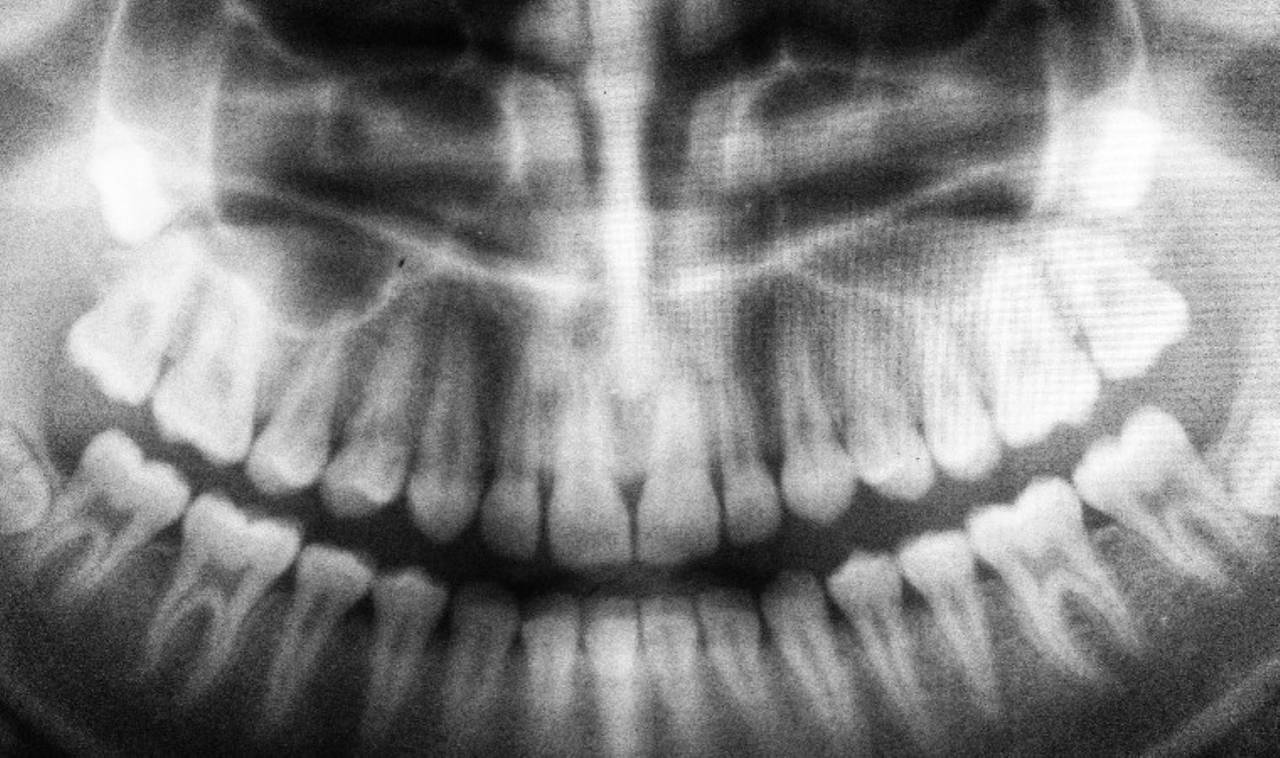

Bruksizm (diş sıkma) tanısını koyma sürecinde diş hekimi durumunun boyutunu değerlendirmek için çeşitli öğeleri kontrol ediyor. Bu kontrol edilen öğeler arasında çene kaslarında hassasiyet, kırık veya eksik dişler gibi belirgin diş anormallikleri ile dişlerde ve yanakların iç kısmında hasar izi ile röntgen yardımıyla altta yatan çene kemiğinde hasar izi aranması bulunuyor. Bu sayede normal bir diş muayenesi, temporomandibular eklem bozukluklarını, diğer diş sorunlarını veya benzer çene veya kulak ağrısına neden olabilecek diğer sağlık bozukluklarını tespit edebiliyor.